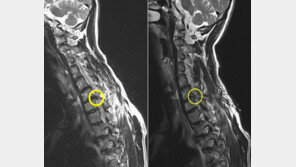

[Health&Beauty]허리-목 디스크, 신개념 고주파 시술로 10분 정도면 끝!

국내 장수 예능 프로그램인 ‘런닝맨’이 중국에서도 인기다. 런닝맨 멤버중 이광수, 김종국과 지석진은 중국에서도 큰 주목을 받고 있다. 이러한 가운데 최근 런닝맨 멤버들이 허리, 목 디스크로 고생하다 고주파 시술을 받고 정상적인 활동을 할 수 있었다는 소식이 중국으로 전해지면서 또 하나…

목과 팔이 아프면 흔히 목디스크가 아닐까 생각하는 경우가 많습니다. 하지만 목디스크 원인도 있지만 사실 근육 문제가 더 많습니다. 이 외에도 디스크의 뼈 부착 부위나 인대 또는 관절 등에 의해 목통증이 생길 수도 있습니다. 목이 아프고 팔이 저리는 목디스크는 우선 약물, 물리치료, 견…